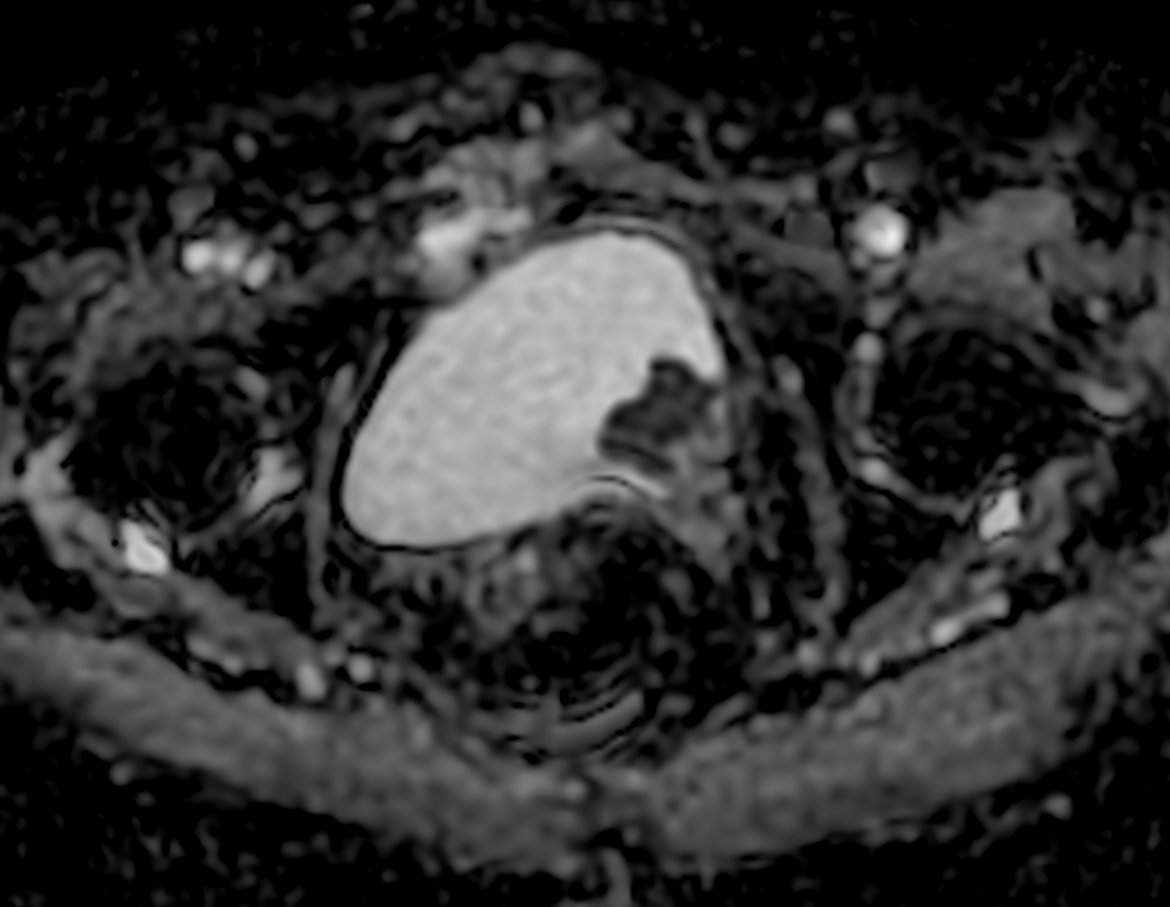

Patient with bladder cancer. The ExamCard includes techniques for motion reduced imaging (MultiVane XD), 3D TSE imaging (PelvisVIEW) allowing for multiple image directions in one single scan, a multi-phase contrast-enhanced sequence (4D FreeBreathing) to improve imaging confidence and Compressed SENSE to accelerate the entire exam.

DWI b1000

DWI b1000 (ADC)